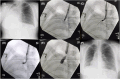

Endobronchial tuberculosis (EBTB) presents significant clinical challenges, particularly when complete bronchial obstruction occurs. In this case, a young woman with right main bronchus occlusion due to tuberculosis (TB) was treated using a novel approach. Instead of using a traditional rigid bronchoscope, a flexible approach was adopted. Under precise fluoroscopic guidance, a 21-gauge transbronchial aspiration needle was used to puncture the obstruction, allowing passage of the guidewire and subsequent balloon dilation. The use of virtual bronchoscopy, developed using computed tomography scans, ensures safe navigation around critical vascular structures. Postoperatively, the patient showed significant symptomatic improvement without complications. This innovative approach not only demonstrates the efficacy and safety of using biopsy needles and virtual bronchoscopy for managing complete bronchial obstructions in EBTB but also opens the door for future innovative solutions in such complex cases.